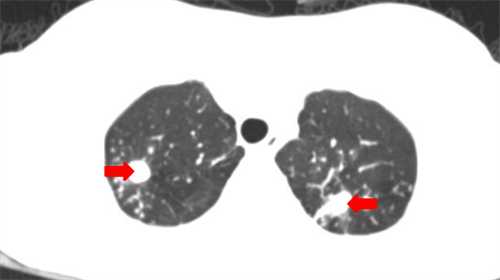

CT示小美(化名)双肺有多发病灶

刚入院时,小美高热,双下肢皮肤溃烂、水肿、营养差,学生儿童结核科主任周海依迅速组织皮肤科、肺外结核科、病理科、呼吸科、感染科、营养科等多学科会诊。医生为小美进行了皮肤活检,确诊其患有皮肤结核,随即迅速为她制定了个性化的治疗方案,每天对皮肤创面进行清创及换药。